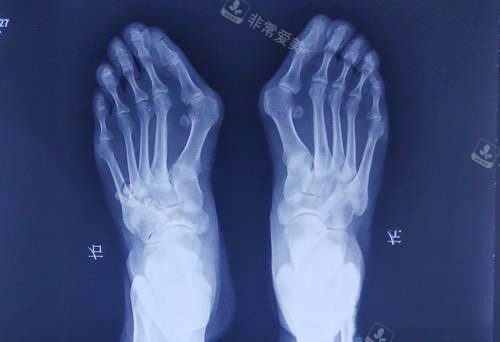

大脚骨拍片

大脚骨,医学上称为拇外翻,不仅影响脚部美观,还会导致疼痛、行走不便等问题。